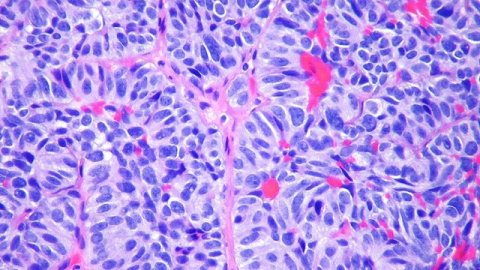

Las células tumorales circulantes (CTC) son células cancerosas que dejan un tumor primario y entran en el torrente sanguíneo, en su camino hacia la siembra de metástasis a distancia. Estas llamadas CTC se pueden encontrar en la sangre de pacientes como células individuales o grupos de células.

Los investigadores suizos han descubierto que la formación de grupos de CTC conduce a cambios epigenéticos clave que facilitan la siembra de metástasis. Estos cambios permiten a estos grupúsculos de células imitar algunas propiedades de las células madre embrionarias, incluida su capacidad para proliferar y retener las capacidades de formación de tejidos. Los científicos también han demostrado que estos cambios epigenéticos son completamente reversibles tras la disociación de los grupos de CTC.